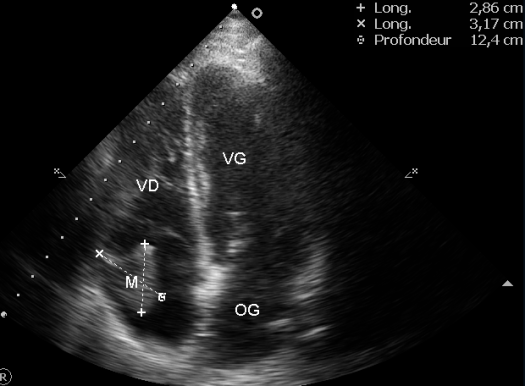

Encore une bien belle image derrière laquelle se cache malheureusement un drame individuel.

Il s’agit d’un LMNH B avec une manifestation tumorale intra cardiaque, dans l’oreillette droite pour être plus précis.